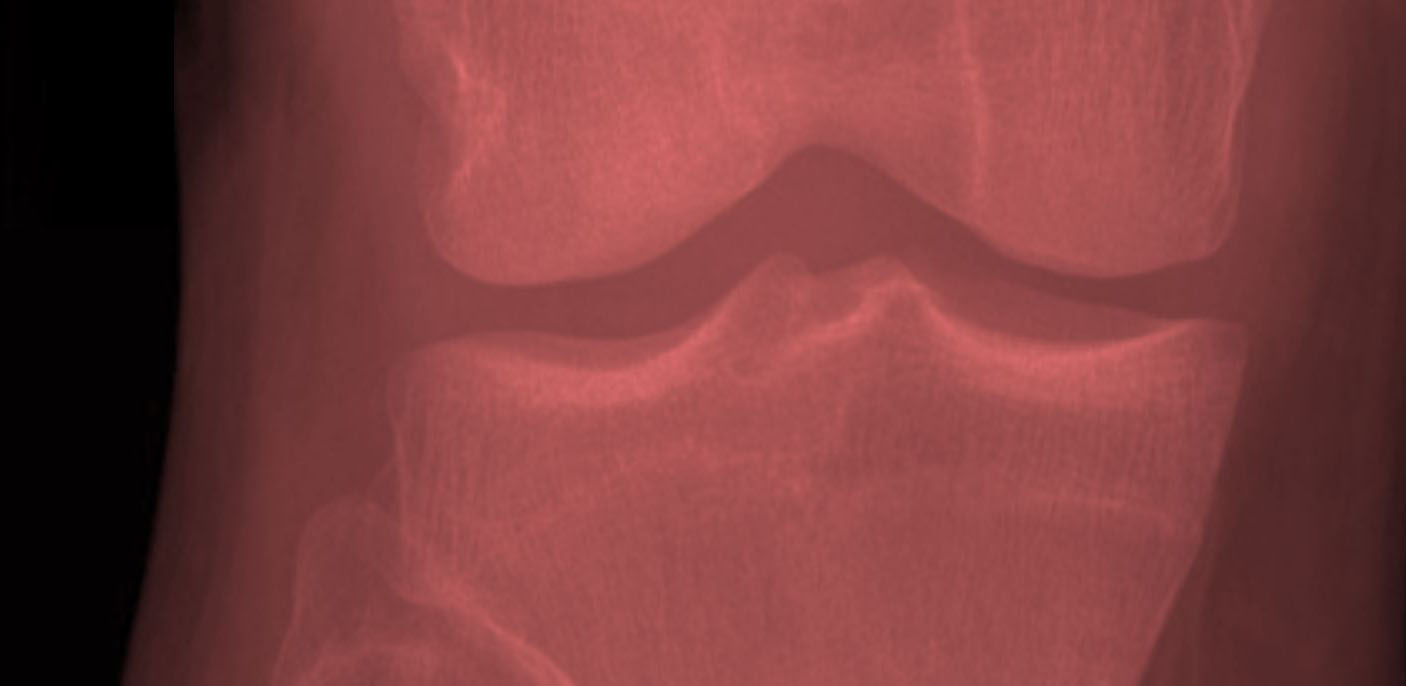

The Forgotten Joint Scores are based on a novel construct: the patients‘ ability to forget about a joint as a result of successful treatment. We believe this to be the ultimate goal in conservative and operative management of joint conditions. In an ongoing research project we are developing patient-reported outcome (PRO) measures to assess this construct for shoulder, knee and hip joints.

The Forgotten Joint Scores comprise measures for the assessment of joint-specific patient-reported outcome (PRO). These PRO questionnaires focus on patients’ awareness of a specific joint in everyday life. The Forgotten…